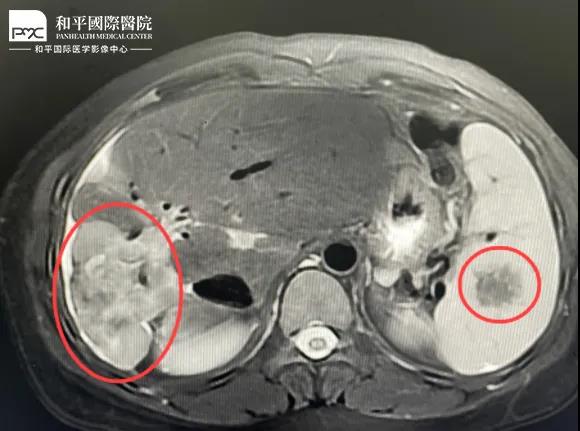

檢查結果對于這家人而言猶如晴天霹靂,經(jīng)核磁共振等相關檢查,當?shù)蒯t(yī)生懷疑是肝癌,建議手術治療。悲痛中,家人們對這樣的結果表示無法接受,想要多去幾家醫(yī)院看看,為了進一步確診,王小姐來到我院醫(yī)學影像中心進行檢查,事情竟發(fā)生了戲劇性反轉(zhuǎn)

根據(jù)影片分析,結合王小姐有系統(tǒng)性紅斑狼瘡的病史,長期服用激素,免疫力低下,近期又有低熱盜汗的癥狀,影像中心執(zhí)行主任侯文杰初步判斷王小姐是得了肝結核,并不是肝癌!

由于肝結核是臨床非常少見的病例,單靠影像診斷是很難診斷正確的,在侯主任的建議下,王小姐做了穿刺活檢,診斷結果的確是肝結核。